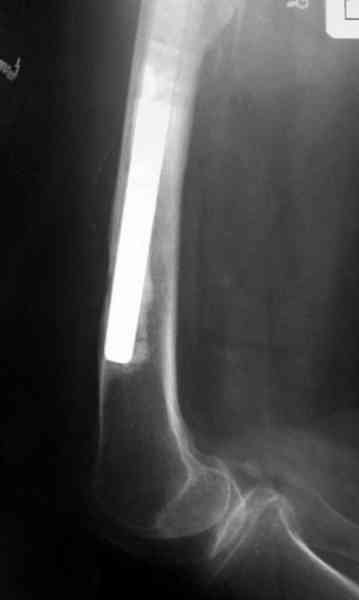

Приготовлен цемент из расчета: Tobramycin 2.4 g (2 флакона), Vancomycin 2 млн (4 флакона) и 2 упаковки цемента с добавлением дополнительного флакона цементной жидкости.

После обработки ацетабулярного компонента, ещё в мягком цементе в полости вертлужной впадины головкой бедренного компонента сделана выемка для головки, чтобы свежий цемент не прилипал к головке. Головку бедренного компонента завернул обычной стерильной фольгой, которую после образования выемки отлепил от головки.

Для спейсера в бедро использовал старый длинный бедренний компонент меньшего диаметра, облепленный со всех сторон цементом с антибиотиком.

№3-6 снимки с осложнением

и последние снимки.